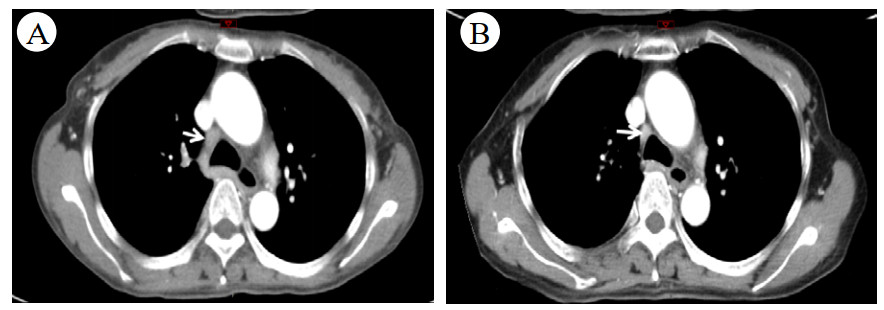

后再因“反复发热、多关节痛7月、皮疹3月”于2019-09-17入住本院风湿科。入院当天体温36.5℃,心率106次/min,呼吸20次/min,血压118/75 mmHg。步态正常,自主体位。左颈部肿大淋巴结。四肢和背部可见紫癜样皮疹,按压部分褪色,伴抓痕。腹软,肝脾未及。图 2为2019-09-21胸部CT结果,箭头所指为肿大淋巴结。

| 图 2 胸部CT示纵膈淋巴结改变 |

经过上述激素联合免疫抑制剂方案治疗,患者病情无改善,再次出现“发热、咳嗽”加重而就诊于当地医院,考虑肺部感染予泰能及莫西沙星静滴治疗11 d,效果欠佳并加重,鼻导管吸氧下动脉血氧饱和度仅及92%左右,故于2020-01-17转入本院ICU二科进一步诊治。入室时神志清晰,检查合作,浅表淋巴结未触及,腹软,上腹压痛。入室检查:血常规WBC 6.09×109,RBC 3.94×1012,Hb 107 g/L, PLT 33×109。总蛋白51.4 g/L,白蛋白24.16 g/L,总胆红素43 g/L,丙氨酸氨基转移酶339 U/L,门冬氨酸氨基转移酶191 U/L,肌酐34.87 umol/L,胆碱酯酶1346 U/L,降钙素原3.28 ng/mL,C反应蛋白193.5 mg/L,免疫指标阴性。D-DII 18 240 ng/mL,PT 17.1 s,APTT 42.8 s,FIB 5.08 g/L。CD4/CD8 > 1.25∶1。胸部CT示双肺间质广泛增厚并见多发斑片影,双肺肺门及纵隔见增大淋巴结,较图 2中影像增大、部分融合,见图 3。

| 图 3 2020-01-18 CT检查影像示纵膈的改变 |

入室诊断:发热查因:结节病?腹膜炎,肺部感染。处理措施包括应用抗生素前行病原学检查;暂予泰能及替考拉宁抗感染,并加强支持治疗。但病情改善不明显。入院第4天(2020-01-21)收到血及腹水培养结果:马尔尼菲篮状菌。修正诊断:马尔尼菲篮状菌感染;肺部感染;腹腔感染;肝功能损伤;胸腔积液;腹腔积液。立即给予两性霉素B治疗。首剂15 mg, 每日增加5 mg, 第4日30 mg, 同时患者热退,胸腹腔积液减少,肝功能好转,凝血功能紊乱纠正,PLT稳步提高。2020-01-31转到呼吸科进一步治疗,两性霉素B疗程满2周,累计量480 mg后序贯伊曲康唑口服治疗,治疗12 d后纵膈淋巴结缩小,患者痊愈出院,出院前CT检查见图 4,WBC等指标变化见图 5。

| 图 4 出院前2020-02-03 CT检查影像示纵膈变化 |

于2022-08-31进行电话随访,患者目前无发热及头痛。遵医嘱定期门诊复诊,初期服用伊曲康唑口服液半年余,即停药至今。无不适。出院后随访肺部CT见图 6。

| A:2020-06-29检查;B:2020-10-28 图 6 出院后CT检查影像示纵膈改变 |